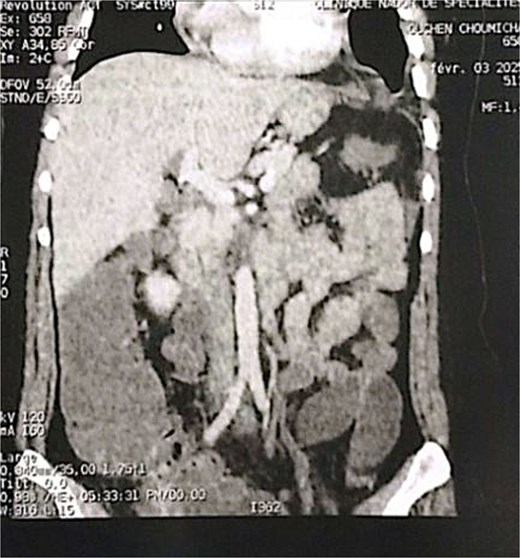

A 29-year-old female, with a history of cesarean section performed three months prior and no history of thoracoabdominal trauma, was admitted to the emergency department for an occlusive syndrome characterized by complete cessation of bowel movements and flatus, associated with vomiting, without other digestive or respiratory symptoms. On examination, the patient was conscious, haemodynamically and respiratorily stable. Abdominal examination revealed marked distension with epigastric tenderness, and digital rectal examination demonstrated an empty rectal ampulla. An initial plain abdominal radiograph, performed in the standing position and focused on the diaphragmatic domes, demonstrated colonic and small bowel distension with multiple air–fluid levels (Fig. 1). Subsequently, a thoraco-abdominopelvic CT angiography was performed, revealing a 3 cm left colonic herniation into the thoracic cavity through a partial posterolateral diaphragmatic rupture, associated with moderate left-sided pleural effusion (Figs 2–4). The herniation caused colonic stenosis at the diaphragmatic defect, with upstream distension of small bowel loops, the stomach remaining in its anatomical position (Fig. 5). These findings were consistent with acute intestinal obstruction secondary to a left-sided diaphragmatic hernia. Surgical management consisted of reduction of the herniated contents, assessment of their viability, and closure of the diaphragmatic defect using interrupted nylon sutures (sizes 2/0 and 0) (Fig. 6). Double drainage was instituted: a 28 Fr posteroinferior thoracic drain inserted through a dependent incision in the 5th intercostal space, and a Jackson–Pratt abdominal drain placed in the rectouterine pouch (Douglas’ pouch).

Coronal section of an abdominal-pelvic angiogram showing a strangulated Bochdalek hernia with colonic and omental contents.